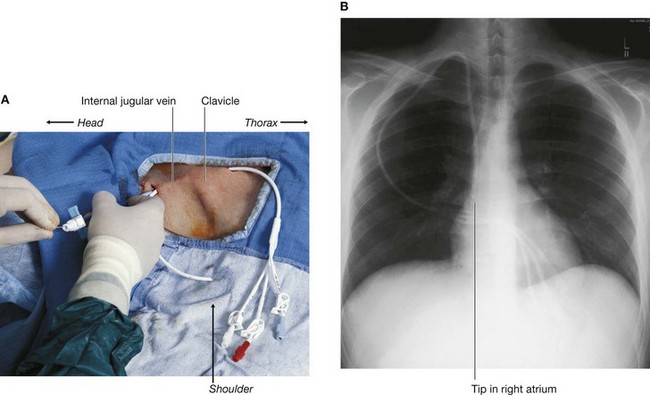

In the clinic

Central venous access

In most instances, access to peripheral veins of the arm and the leg will suffice for administering intravenous drugs and fluids and for obtaining blood for analysis. In certain circumstances it is necessary to place larger-bore catheters in the central veins, for example for dialysis, parenteral nutrition, or the administration of drugs that have a tendency to produce phlebitis.

“Blind puncture” of the subclavian and jugular veins to obtain central venous access used to be standard practice. However, subclavian vein puncture is not without complications. As the subclavian vein passes inferiorly, posterior to the clavicle, it passes over the apex of the lung. Any misplacement of a needle into or through this structure may puncture the apical pleura, producing a pneumothorax. Inadvertent arterial puncture and vein laceration may also produce a hemopneumothorax.

A puncture of the internal jugular vein (Fig. 8.156) carries fewer risks, but local hematoma and damage to the carotid artery are again important complications.

image

Fig. 8.156 Placing a central venous catheter in the neck. A. Clinical procedure. B. Chest radiograph showing that the tip of the catheter is in the origin of the right atrium.

Current practice is to identify major vessels using ultrasound and to obtain central venous access under direct vision to avoid any significant complication.